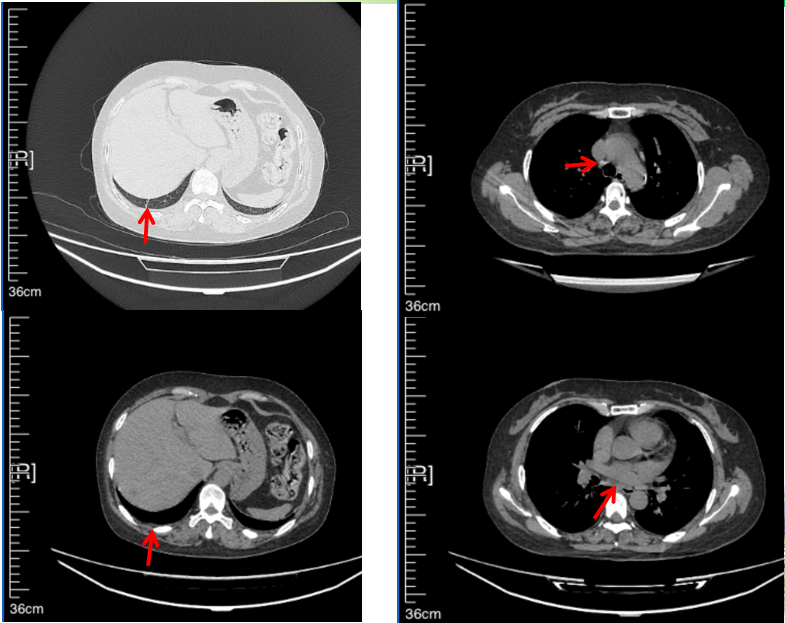

56岁,女性,无吸烟史饮酒史,既往体健。2023年02月患者体检发现肺占位性病变,胸部增强CT:右肺下叶后基底段结节;右侧锁骨上及纵隔内多发淋巴结肿大。PET-CT:右肺下叶周围型肺癌可能性大;1R、2L、3P、4R、4L及7组淋巴结转移可能性大。2023年02月就诊于本院胸外科行超声胃镜下纵隔肿物穿刺活检术,病理:结合免疫组化,符合肺腺癌。行NGS基因检测:EML4:exon20-ALK:exon20融合。PD-L1(克隆号22C3)TPS=55%。

2023年2月20日基线检查

2024年6月复查PR(最佳疗效)

2024年12月复查维持PR

2025年3月复查维持PR